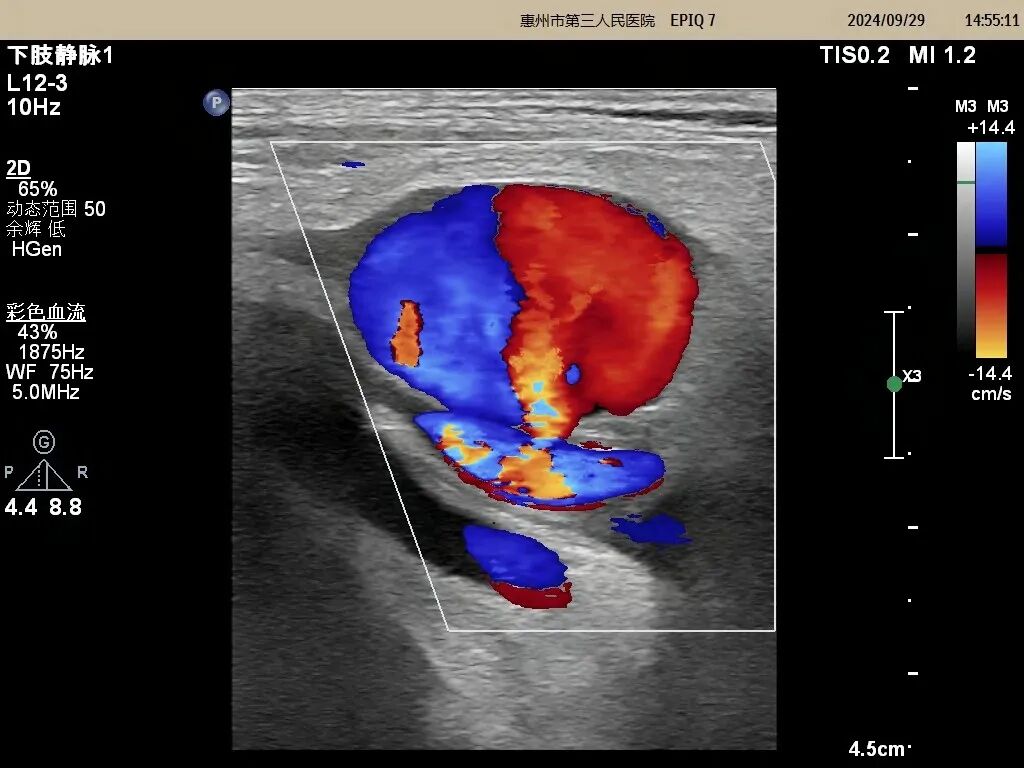

(術前圖片)